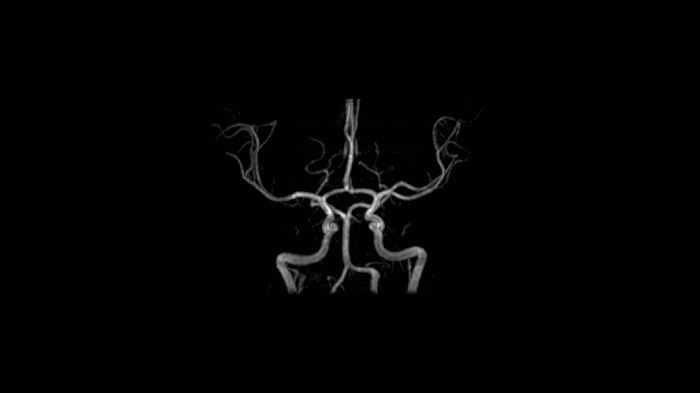

Time-of-flight angiography

Non-contrast enhanced angiography of the cranial vessels is used to detect vessel occlusions or aneurysms. High-resolution ToF angiography can also show small arteries for subtle diagnoses.

• Head/Neck Coil

80 cm bore MAGNETOM Free.Max

Image Courtesy: University Hospital Erlangen, Germany | Image-ID: 4aaaa0466